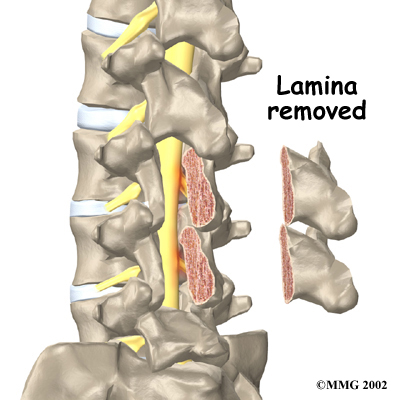

The lamina forms a roof-like structure over the back of the spinal column. When the nerves in the spinal canal are squeezed by a degenerated disc or by bone spurs pushing into the canal, a laminectomy removes most, or all of the lamina to release pressure on the spinal nerves.

Related Document: FYZICAL Central Nampa's Guide to Lumbar Laminectomy

Surgery to take out part or all of a problem disc in the low back is called discectomy. Discectomy is done when the degenerated disc has ruptured (herniated) into the spinal canal, putting pressure on the spinal nerves. Surgeons commonly perform this operation through an incision in the low back. Before the disc material can be removed, the surgeon must first remove part of the lamina. Generally, only a small piece of the lamina is chipped away to expose the problem disc. This is called laminotomy. It usually creates enough room for the surgeon to remove the disc. If more room is needed, the surgeon may need to take out a larger section of the lamina by doing a laminectomy (described above).